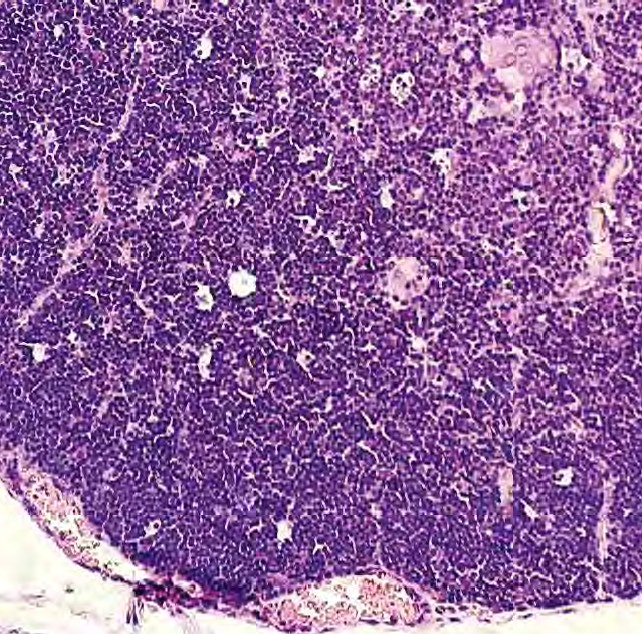

Fig. 2. Rabbit thymus when infected with bacteria P. aeruginosa. Hematoxylin and eosin. Magnification: 10 × 20, H604 Trinocular Unico, USA

Source: made by the authors